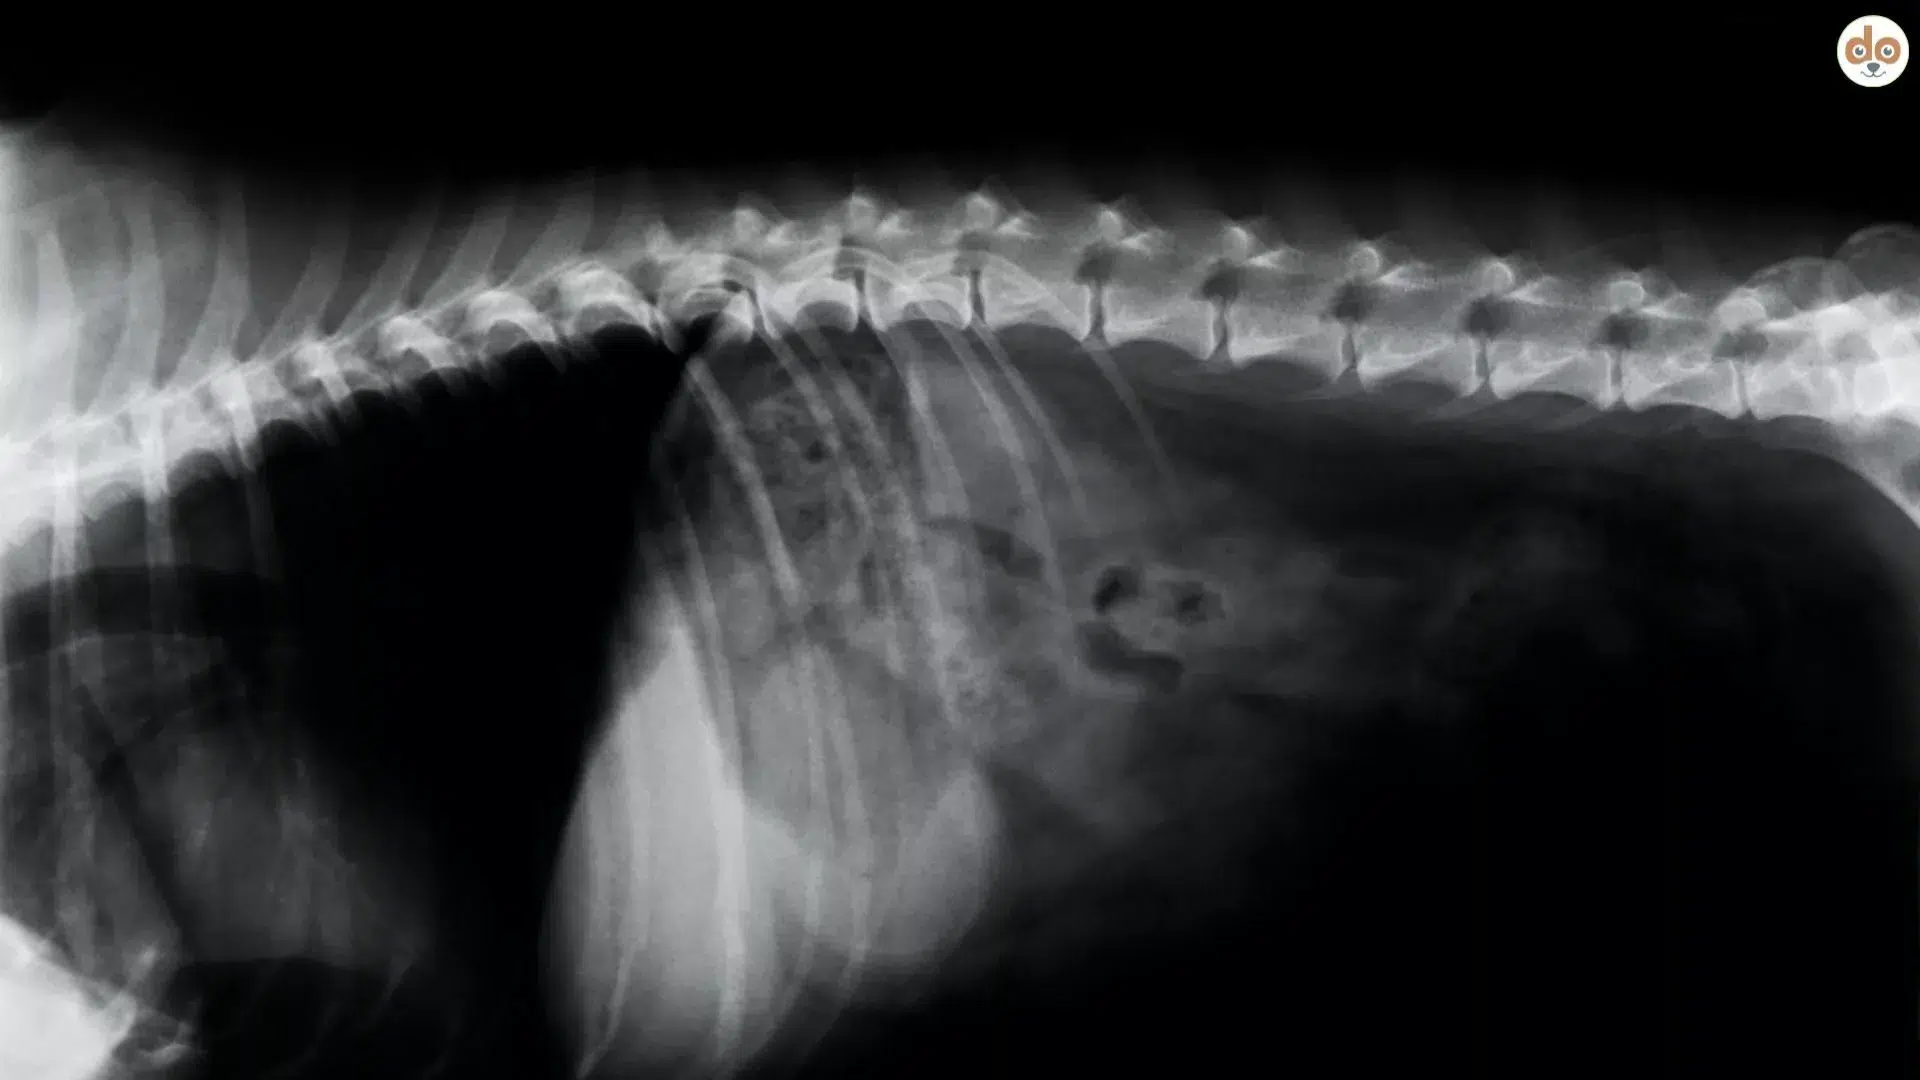

Wenn dein Hund plötzlich schwach wird oder eine Lähmung zeigt, ist das immer ein Notfall. Auch wenn er keine Schmerzen hat, können ernste Ursachen dahinterstecken. Tierärzt:innen, idealerweise mit Spezialisierung in Neurologie, untersuchen zunächst genau, welche Abschnitte des Rückenmarks betroffen sind. Eine MRT-Untersuchung ist dabei der Goldstandard: Sie zeigt, ob tatsächlich eine Durchblutungsstörung (Rückenmarksinfarkt) vorliegt oder ob andere Probleme wie ein Bandscheibenvorfall, eine Entzündung oder ein Tumor verantwortlich sind. Typisch für einen Rückenmarksinfarkt ist, dass sich im MRT eine veränderte Region innerhalb des Rückenmarks zeigt, ohne dass dort etwas drückt.